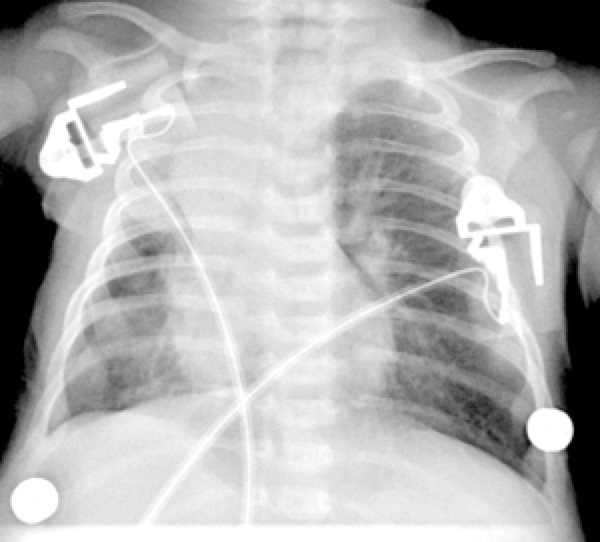

THYMUS OU BPN

Chercher un bronchogramme aérique!!!!